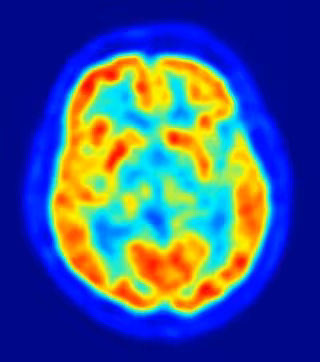

El tratamiento con metadona puede afectar a las células nerviosas del cerebro a largo plazo, según ha mostrado un reciente estudio del Instituto Noruego de Salud Pública. De esta forma, este trabajo continúa la senda de otros anteriores que consideraban que esta droga "afectan al funcionamiento cognitivo".

En este sentido, los expertos confirman que capacidades como el aprendizaje y la memoria pueden verse perjudicadas. Para ello, y dada la imposibilidad de llevar a cabo estudios controlados en pacientes con metadona, los investigadores emplearon ratas durante los ensayos clínicos.

En los mismos, los animales recibieron una dosis diaria de metadona durante tres semanas, tras las que se les extrajo las áreas del cerebro donde se ubican el aprendizaje y la memoria. Al analizar los posibles cambios o daños neurobiológicos establecidos, los expertos descubrieron que se originó una reducción del 70 por ciento en una molécula importante en estas capacidades.

Tras producirse este efecto, tanto en el hipocampo como en la parte frontal del cerebro, los científicos también observaron que esta circunstancia se mantenía una vez eliminada la droga del organismo, lo que "puede ser motivo de preocupación", señalan. No obstante, un estudio paralelo de la Universidad Southwestern de Texas (Estados Unidos) ha concluido que la metadona no tiene incidencia en la generación de nuevas células nerviosas.